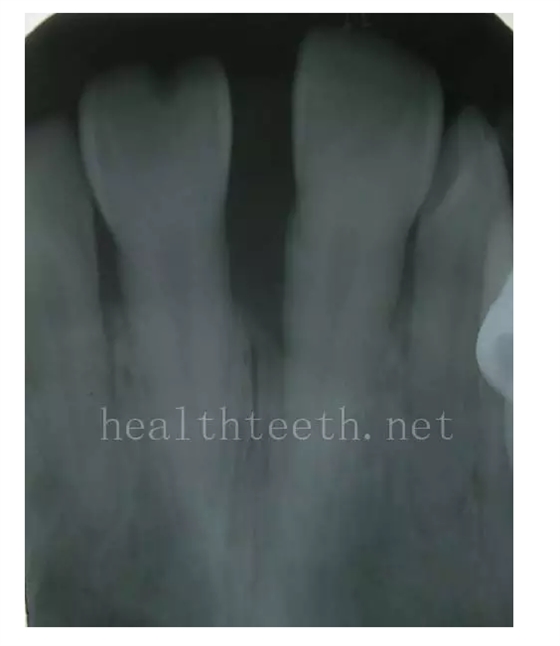

12歲孩子門牙的齲齒

七、牙齒的外傷

牙冠折斷

牙根折斷